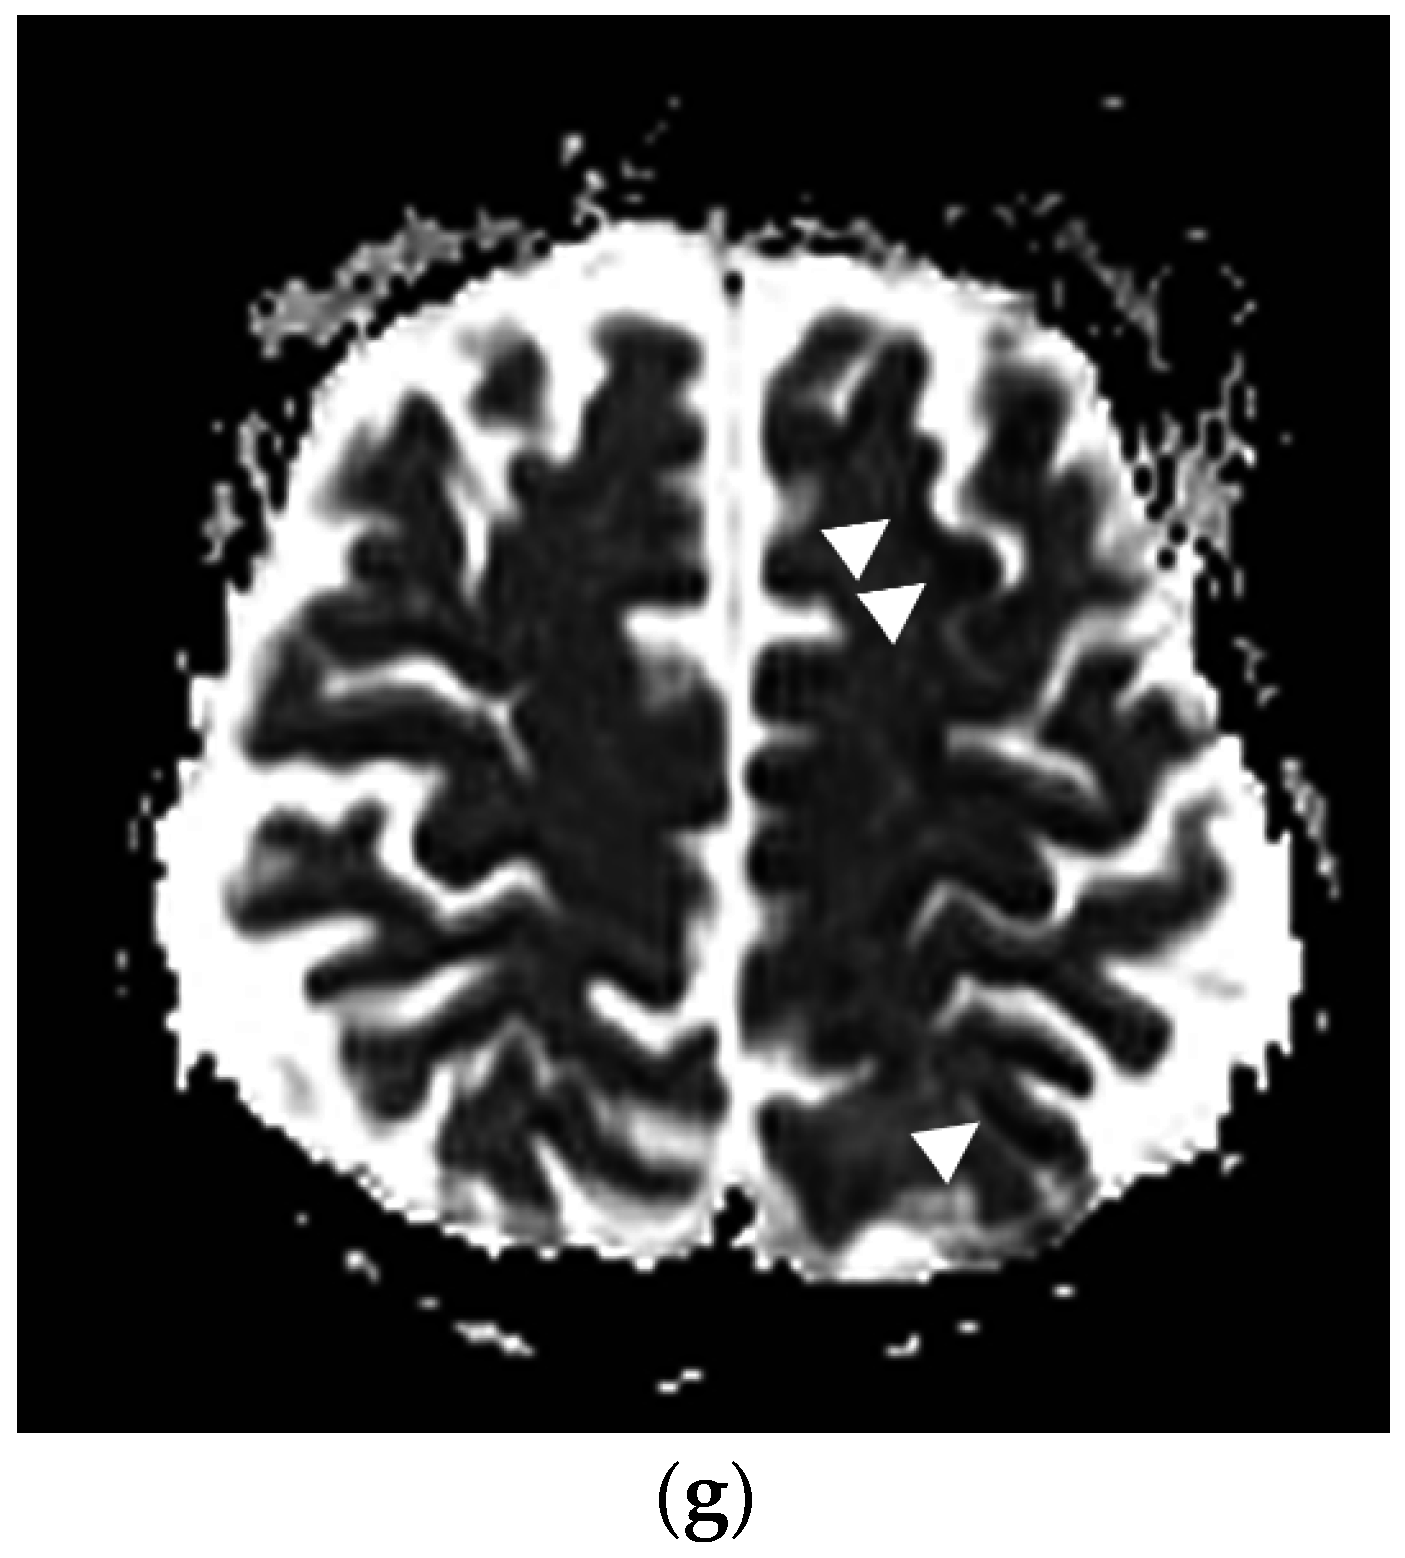

Figure 4.

Following the placement of right internal jugular tunneled Hickman line, a 76-year-old man developed an episode of desaturation, tachycardia, and non-responsiveness. Subsequently, an immediate CT of brain, neck and chest was performed and gas was found in the left cavernous sinus (a,b) and within a left parietal sulcus (c); it was felt to represent air in a vessel, possibly a pial vein. There was also a large amount of air surrounding the right internal jugular vein (d); with a partially visualized central venous catheter (*). A brain MRI was performed showing FLAIR hyperintensity in multiple regions (e) with evidence of restricted diffusion (f); and corresponding low signal (arrowheads) on the apparent diffusion coefficient (ADC) images (g). The patient received a single treatment of hyperbaric oxygen but died 8 days later.